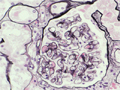

- ★(4)IgA nephropathy

Microscopic findings (HE, high power view): Slight expansion of the mesangium is noted (area within red dotted line).